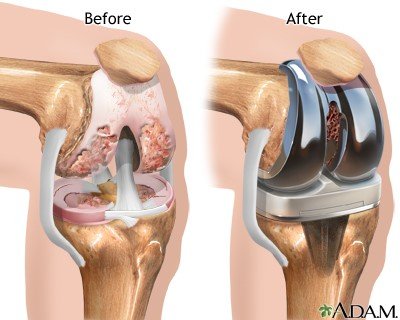

KNEE REPLACEMENT

What is a knee replacement surgery? Knee…